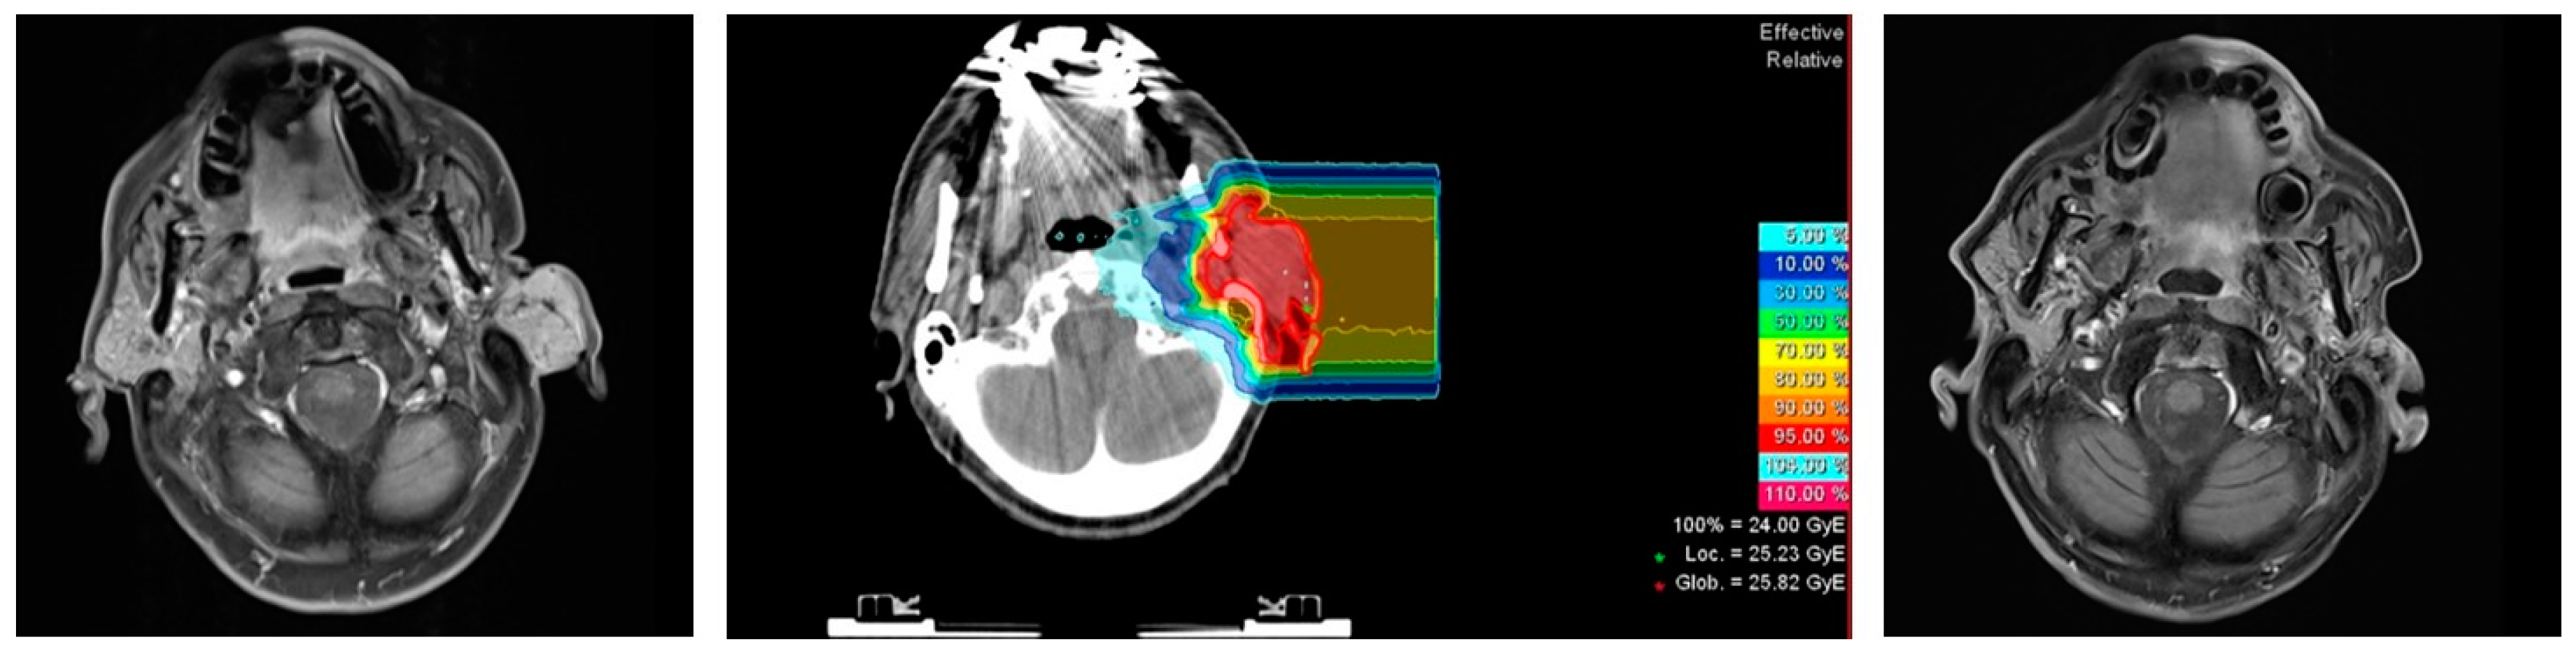

2.2. Treatment Characteristics

4.2. Radiotherapy

| Carbon Ion Radiotherapy | metric |

| Median GTV in cm3 (range) * | 37 (15–182) |

| Median CTV1 in cm3 (range) | 106 (32–594) |

| Median prescribed single dose in Gy RBE-weighted dose (range) | 3 (3–3) |

| Median prescribed total dose in Gy RBE-weighted dose (range) | 24 (18–24) |

| Number of beams (n) | |

| 1 | 7 |

| 2 | 8 |

| IMRT | |

| Median CTV2 in cm3 (range) | 270 (99–943) |

| Median prescribed single dose in Gy (range) | 2 (2–2) |

| Median prescribed total dose in Gy (range) | 50 (50–54) |

| Median cumulative dose in Gy RBE-weighted dose | 74 (72–74) |